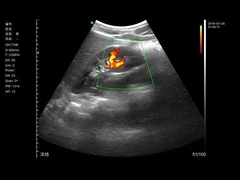

Wuxi Biomedical Technology Co., Ltd.

جودة المحمولة الموجات فوق الصوتية سكانر, الماسح الضوئي بالموجات فوق الصوتية المحمولة manufacturer from China